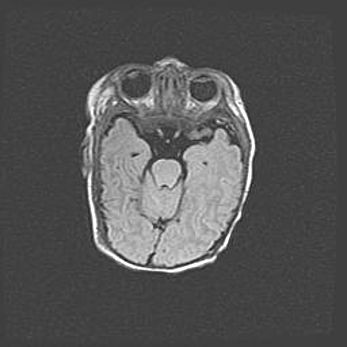

Сообщающаяся гидроцефалия. Кистозная энцефаломаляция головного мозга.

Возраст: 3 месяца 4 дня

Вес: 3100 г

Пол: женский

Окружность головы: 34 см

Срок гестации: 31 неделя

Кистозная энцефаломаляция головного мозга - одна из форм поражения головного мозга в детском возрасте. Характеризуется возникновением множественных и распространённых кист в коре, белом веществе и подкорковых образованиях головного мозга у плодов, новорождённых и детей раннего возраста. Развитие кистозной энцефаломаляции связано с внутриутробной асфиксией и гипотонией, родовой травмой, тромбозом синусов, пороками развития сосудов, инфекциями, сепсисом и другими причинами. Наиболее значимые инфекционные агенты: вирусы простого герпеса, цитомегалии, краснухи, токсоплазмы, энтеробактерии, золотистый стафилококк и другие.